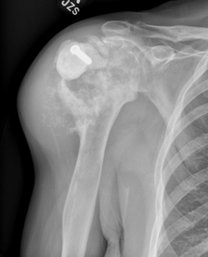

Ακτινογραφίες . Οι βλάβες του χόνδρου μπορούν συχνά να αναγνωριστούν από την ακτινογραφική τους εμφάνιση (πώς φαίνονται σε μια ακτινογραφία).

Στην ακτινογραφία:

- Τα χονδροσαρκώματα έχουν πιο επιθετική ακτινογραφική εικόνα. Η ακτινογραφία θα δείξει καταστροφή του οστού, μια μεγάλη μάζα μαλακών ιστών και πιθανώς ένα κάταγμα.

Επιθετικός όγκος χόνδρου με οστική καταστροφή και μάζα μαλακών ιστών, που συνάδει περισσότερο με χονδροσάρκωμα.